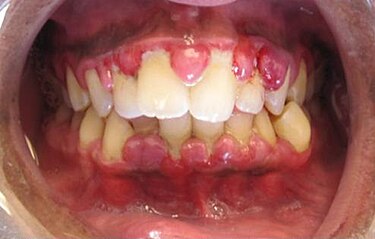

If gingivitis is not treated, it can turn into periodontitis, a more serious gum disease. Periodontitis hurts gums and the bone that holds teeth.

Gums pull away from teeth, making pockets where germs grow. Over time, these pockets damage bone and teeth. Teeth may get loose or fall out.

Signs of Periodontitis :

- Red, swollen, or painful gums

- Bleeding gums easily

- Gums pulling away from teeth

- Loose teeth

- Bad breath or bad taste

- Pus in gums

- Bite changes

Even with treatment, periodontitis cannot be reversed, but dentists can stop it from getting worse.